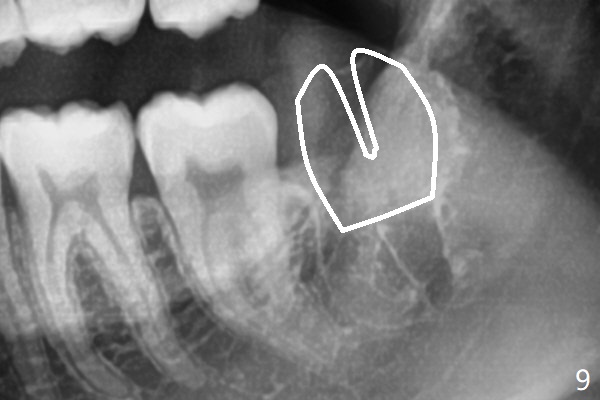

A 19-year-old man returns for #1,16,17 and 32 extraction (Fig.1,2). Because of horizontal impaction of #32 and no bone #31 distal post extraction (Fig.3 *), 3D bond (.5 cc) will be placed in the mesial socket of #32 (Fig.4 red), while Osteogen plug (1/2 (O)) in the distal one. Since there is no bony defect between #17 and 18 after extraction (Fig.5 *), a piece of Osteogen plug (cut half apical) will be inserted in #17 socket, whereas 2 small pieces of Osteogen plug placed in the apical portions (triangle and spindle shaped). Take posterior panoramic X-ray postop (bitewing type, CT format, not XV). There appears bone formation in the socket 5 months postop (Fig.10,11).

Since #32 sockets seem large, extending mesiobuccal (Fig.6), Bond Apatite (1 cc) is placed instead (Fig.7 B), covered by 1/3 of Osteogen plug (O) and sutured with 4-0 PGA. Extraction of #17 is also difficult. As 2 sockets are indistinct, a piece of Osteogen plug with split is placed (Fig.8) upside down (Fig.9 vs. Fig.5). There appears bone formation in the socket 5 months postop (Fig.10,11).